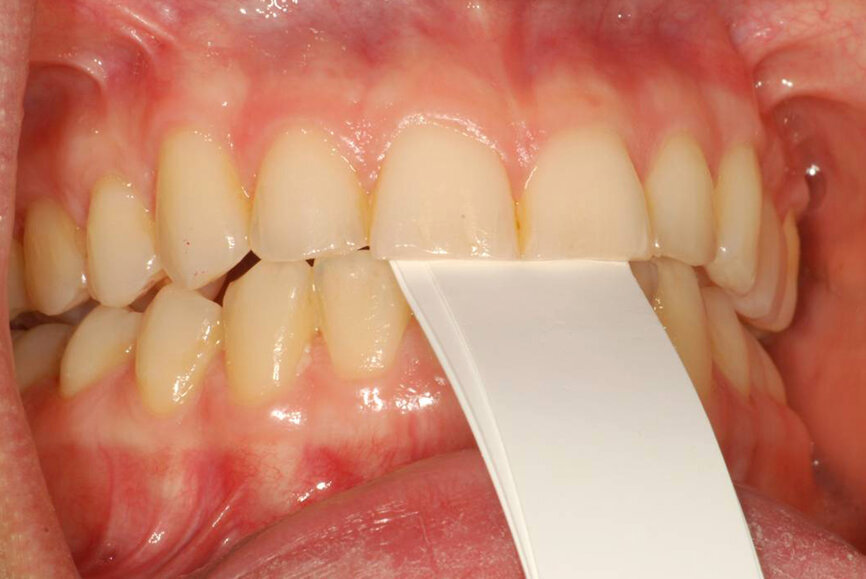

Fig. 13: Intercuspation requiring opening of the vertical dimension for restorative space.

- To obtain restorative space when needed restorations require an opening of the vertical dimension (Fig. 13);[21, 22]